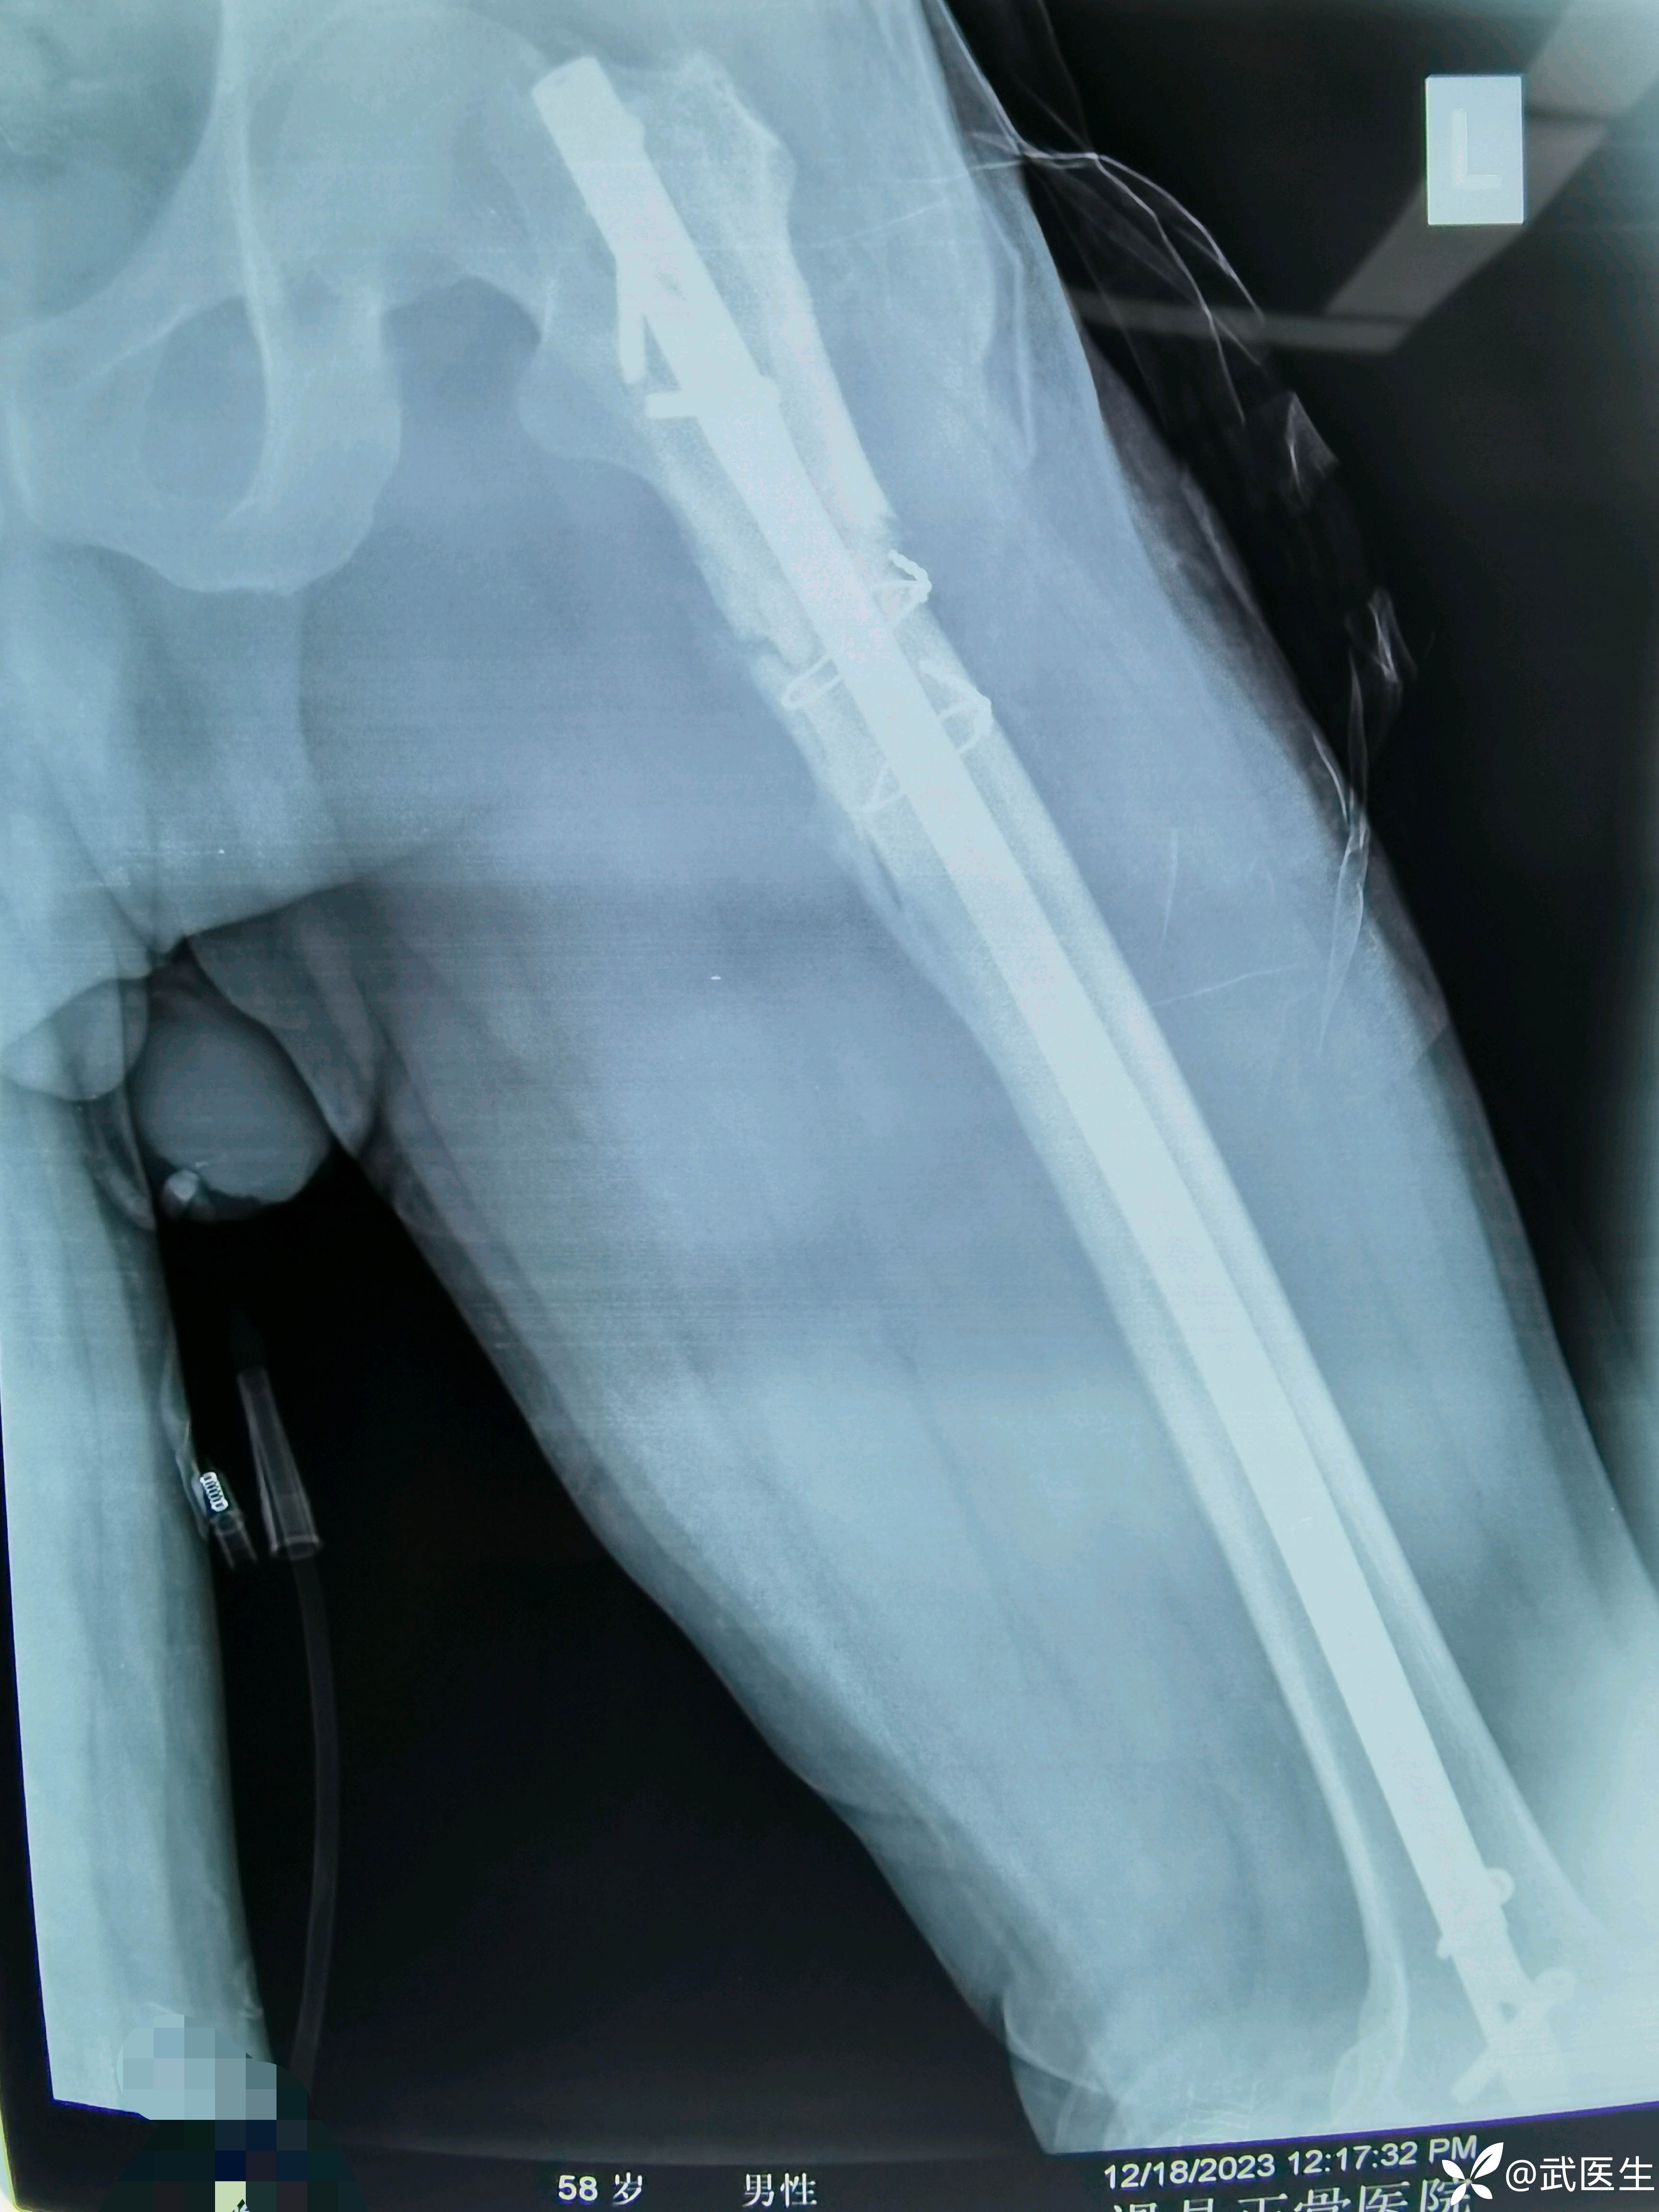

科内会诊讨论,计划1.闭合复位顺行髓内钉2.复位不良则辅助钢板自体髂骨取骨植骨3.钢丝原则上不取。4,不选择单纯钢板内固定。